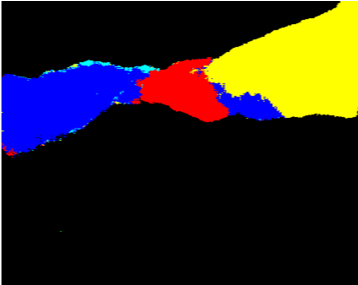

Our challenge was made up of 3 sub-problems. The first was binary instrument segmentation, where each frame was separated into da Vinci Xi instruments and a background class, which contained an ultrasound probe, surgical clips and porcine tissues. The second task was instrument part segmentation, where we scored the participants on whether they could correctly segment each articulating part of the instrument (see Fig. 3). Our final task was to segment and classify the instruments (see Fig. 4).

We provided the first 225 frames of 8 sequences as training data and kept the last 75 frames of those 8 sequences as test data. 2 of the full 300 frame sequences were kept as test sequences. Test labels were kept hidden from the participants. Our datasets contain 7 different robotic surgical instruments. The Large Needle Driver, Prograsp Forceps, Monopolar Curved Scissors, Cadiere Forceps, Bipolar Forceps, Vessel Sealer and additionally a drop-in ultrasound probe, which is typically held in the jaws of the Prograsp Forceps instrument. Samples from the training datasets are depicted in Fig. 2 and examples of the different instrument types are shown in Figure 3 and 4.